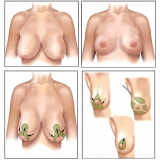

Abdominoplastia com Lipo

Há momentos em que é necessário ter por perto profissionais qualificados e dedicados à pronta recuperação do paciente. A FF Cirurgia Plástica oferece e coloca à sua disposição o que existe de mais atualizado em procedimento cirúrgico para abdominoplastia com lipo. Com o objetivo de levar qualidade à vida dos clientes, a instituição oferece infraestrutura adequada às necessidades de cada um: cuidado médico humanizado, realizado através de dedicação, profissionalismo e amor.